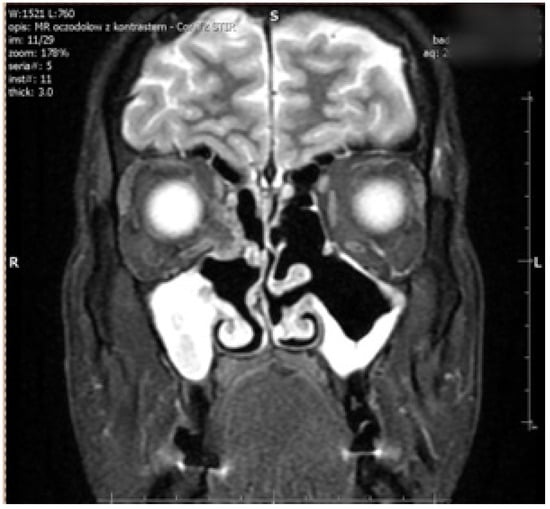

Figure 2. Postoperative coronal MRI scan showing bilateral ethmoidectomy, antrostomy, and uncinectomy in chronic maxillary sinusitis with significant mucosal thickening. MRI scan demonstrates the right medial rectus displacement.

The right side was more commonly affected (five right, two left) (Figure 1). The medial orbital wall was fractured in all but one case (case 5) where the damage involved the inferior wall. Prolapse of the orbital fat and soft tissue into the field of injury were described in all patients who experienced medial wall defect. Air-filled cavities were commonly seen around the injury and the characteristic lesions for conducted endoscopic surgery were visible on all scans (Figure 2).